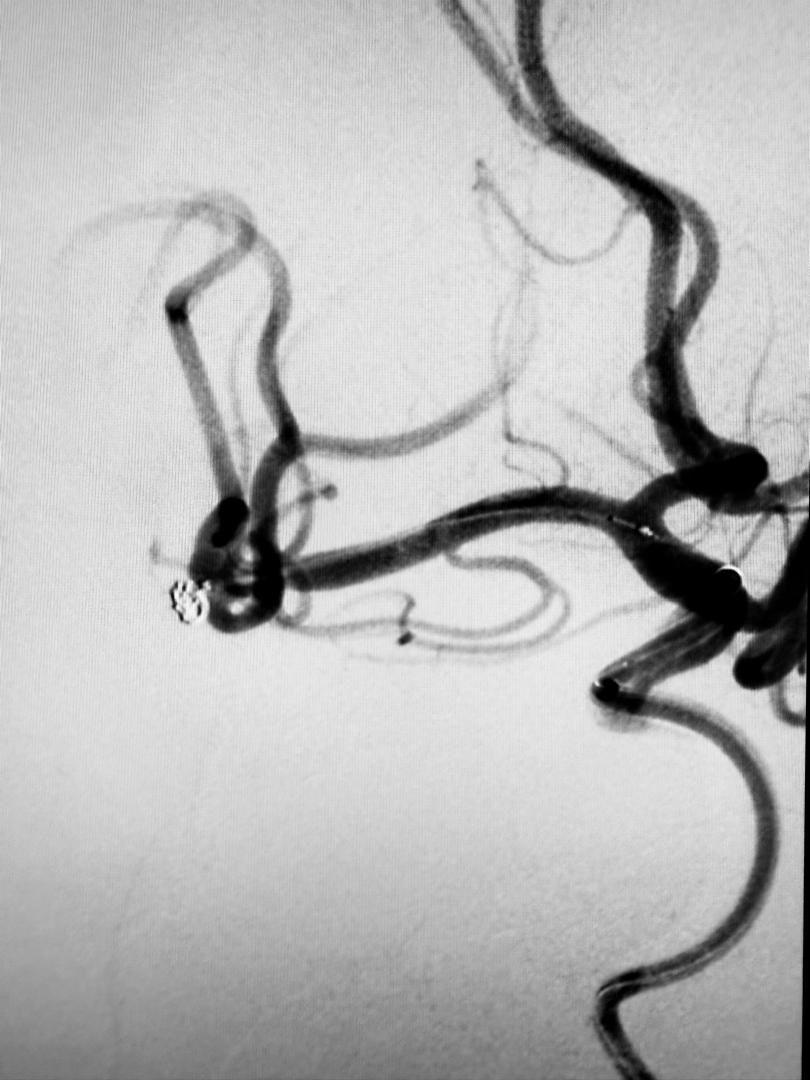

At PCSH, a Digital Subtraction Angiogram (DSA) confirmed the aneurysm’s presence.

“Using a 1.7F microcatheter (with a diameter smaller than 1mm), the team carefully delivered a platinum coil 2mm in diameter and 4cm in length into the aneurysm sac.

“The coil was electrically detached once securely positioned, filling the aneurysm and preventing any further blood flow into it.

“Only the coil remains in the aneurysm, effectively neutralizing the risk of rupture,”